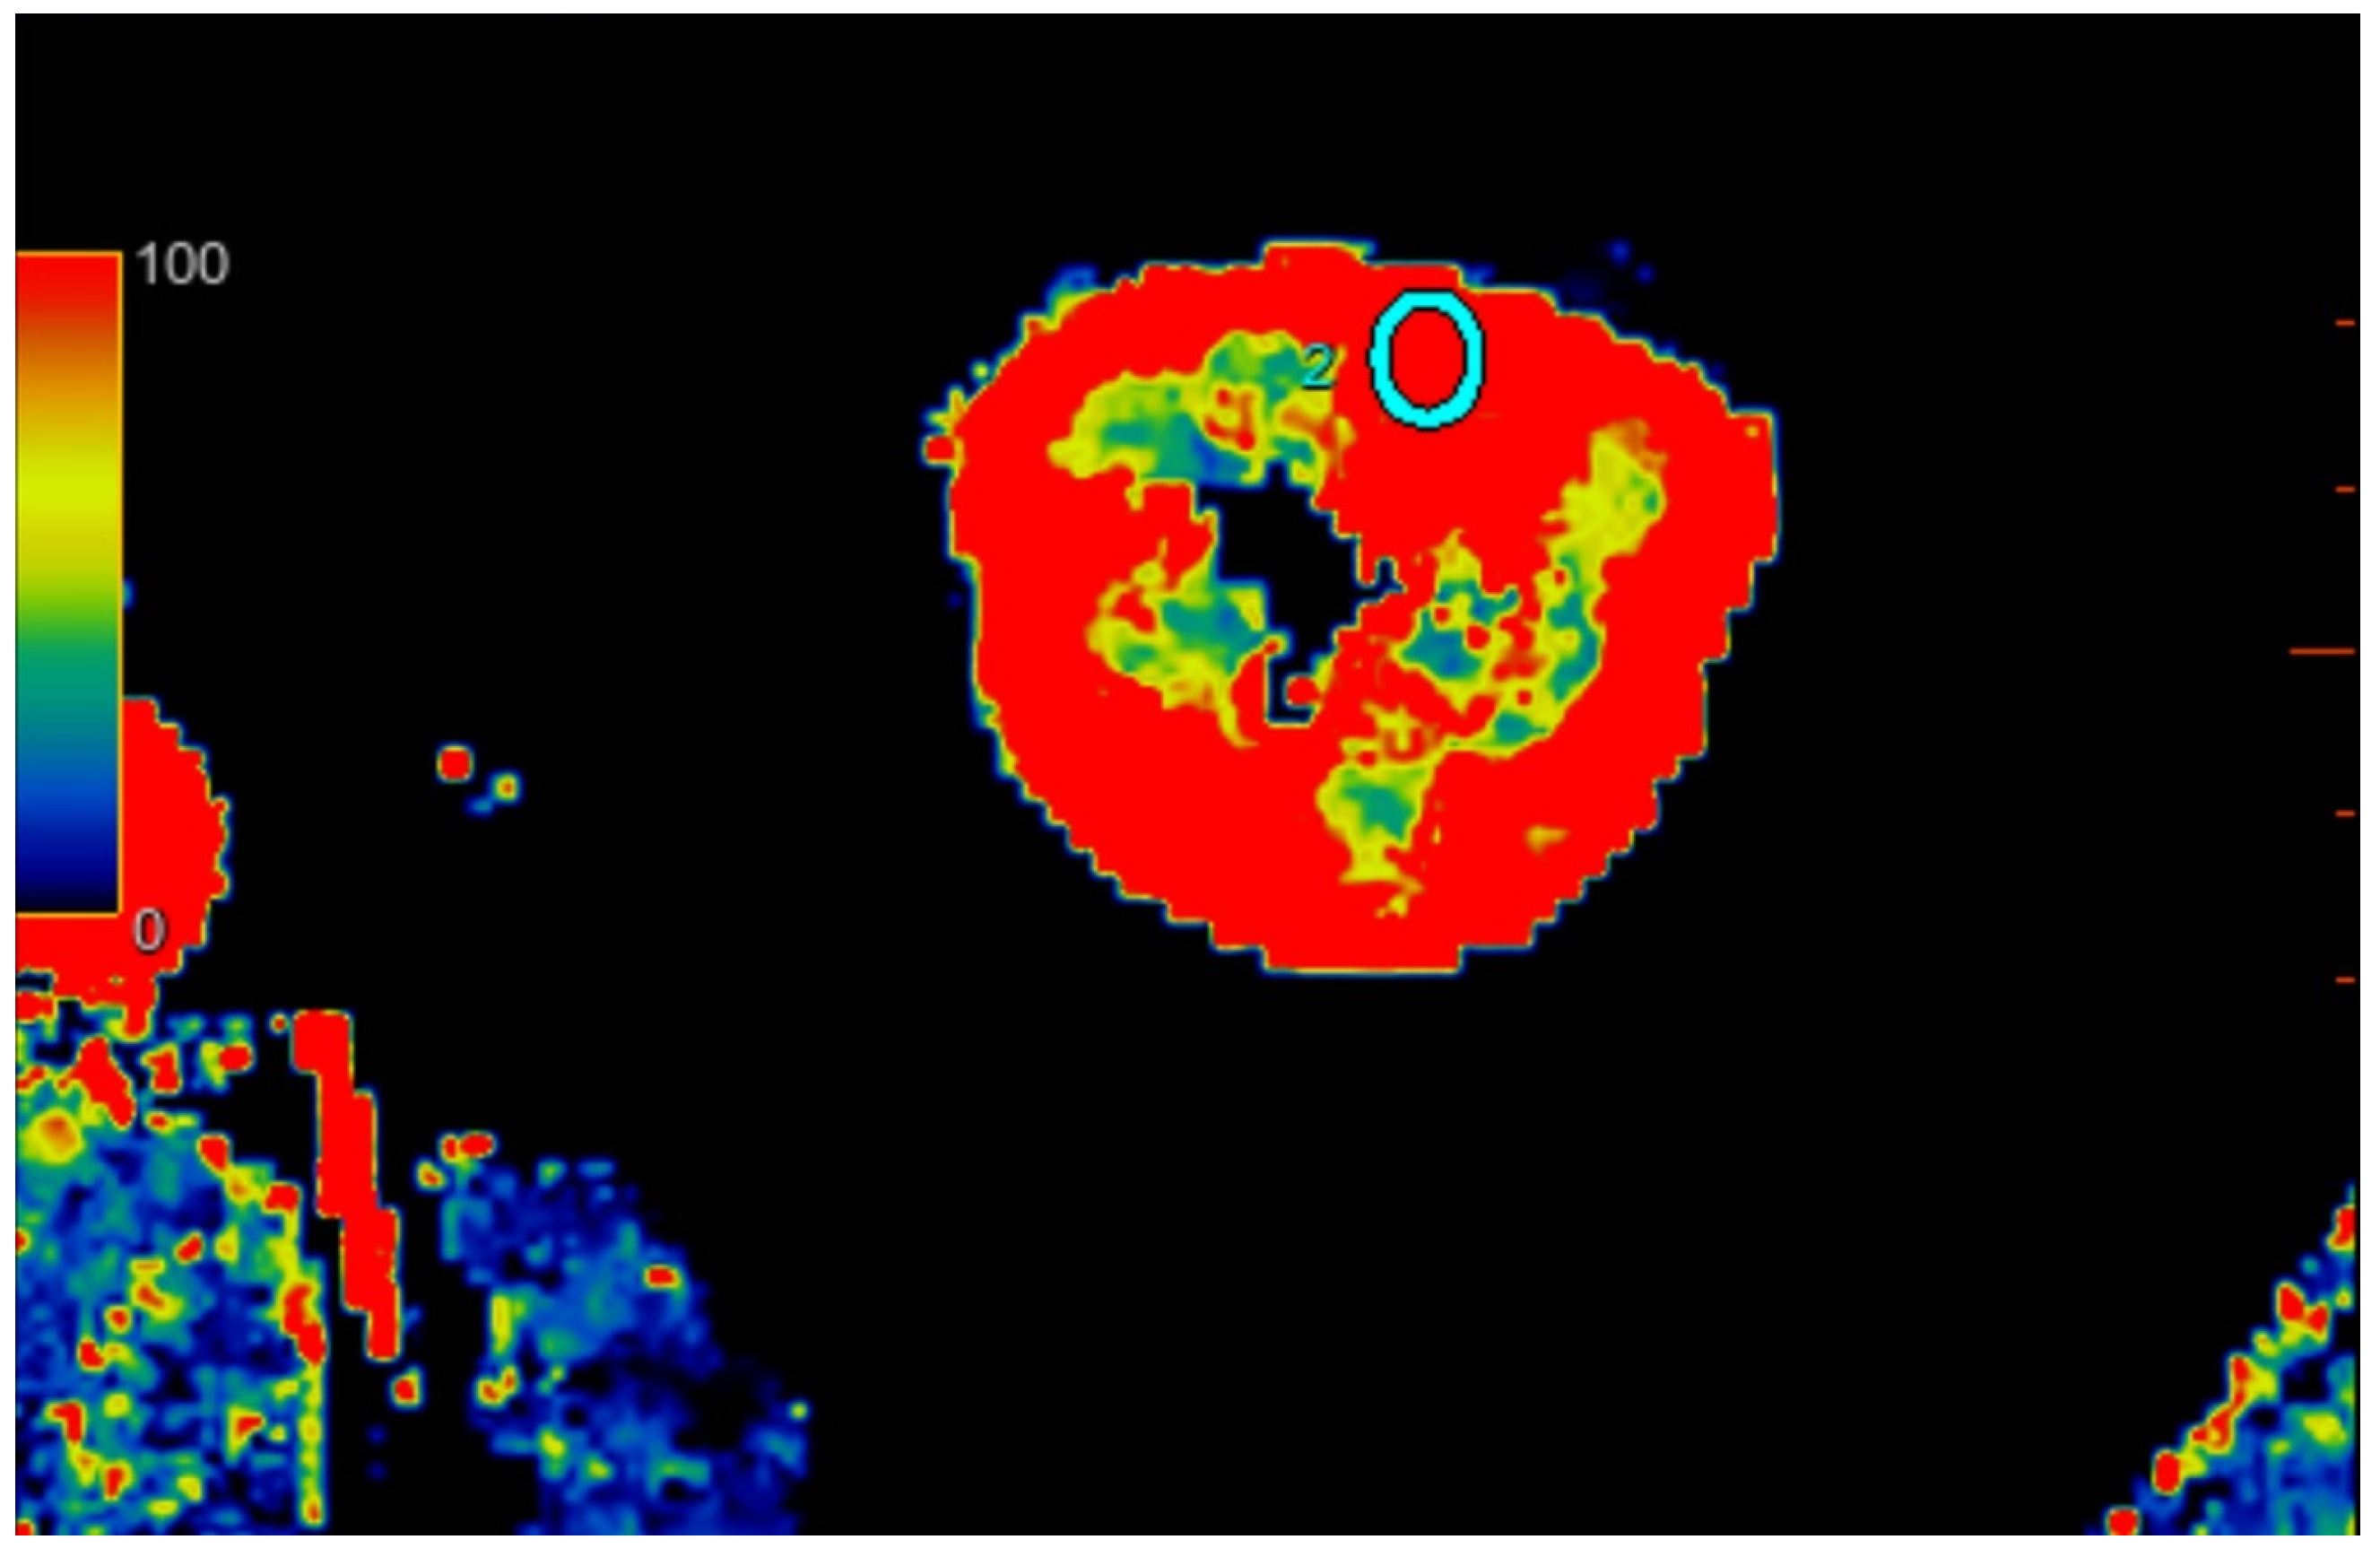

2.2.2. Quantitative Analysis of Perfusion